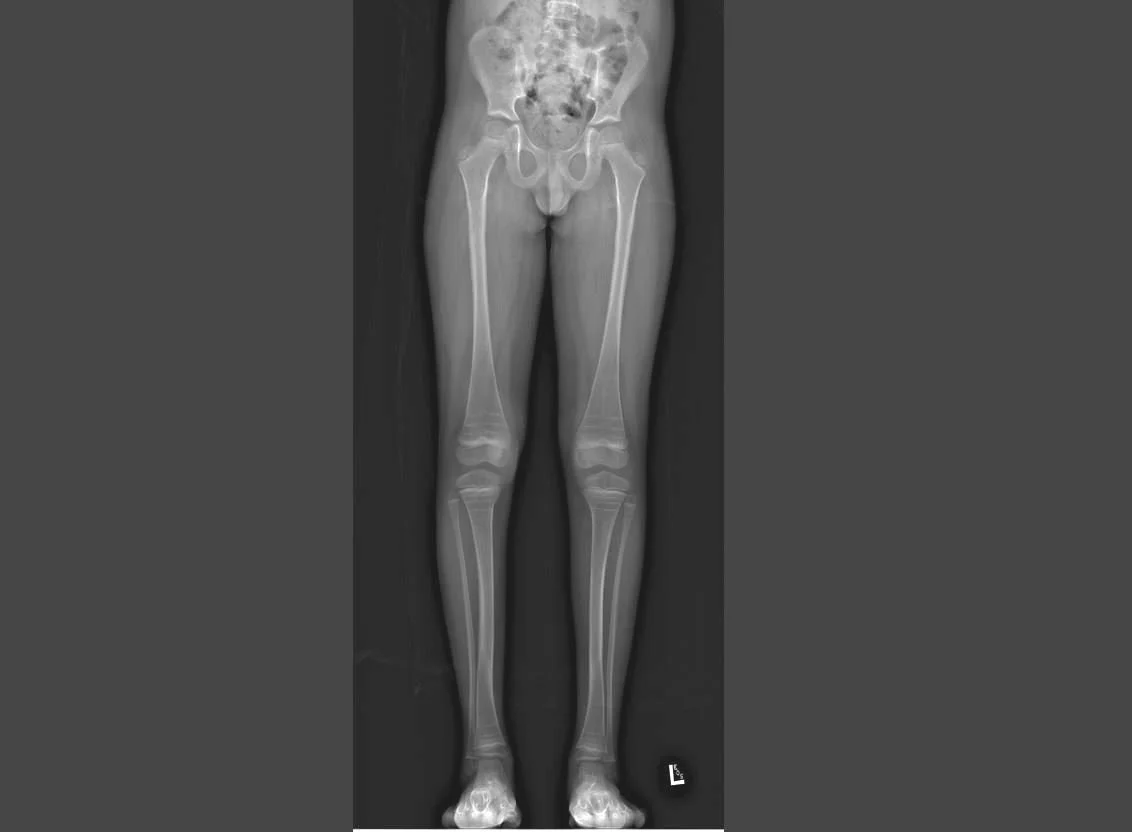

Limb Deformity Database: An Observational Study of Children with Limb Differences

Our limb deformity database, which has over 467 participants to date, allows us to prospectively record outcomes of various treatment procedures for children with limb deformities. This study will enable us to compare the trajectory of treatment of congenital and acquired limb deformities, such as time in corrective frames, number of surgeries, and complications and help us determine any changes required in our ongoing clinical care based.

The International Limb Differences Registry (ILDR) pools patients together with a wide spectrum of limb differences to collect data for current and future studies. The study aims to develop an international registry that encompasses the entire diagnostic spectrum, from follow-up to skeletal maturity. Currently, we are recruiting patients for our Osteogenesis Imperfecta registry.

The Global Pediatric Orthopaedic Implant Safety and Efficacy (POISE) Registry aims to understanding the health outcomes of pediatric orthopaedic implant devices and evaluating their safety and efficacy. This registry is multi-centre and collaborative with many sites around the world. Currently at BC Children’s Hospital, we have 99 participants enrolled, 54 of which are deformity correction participants.